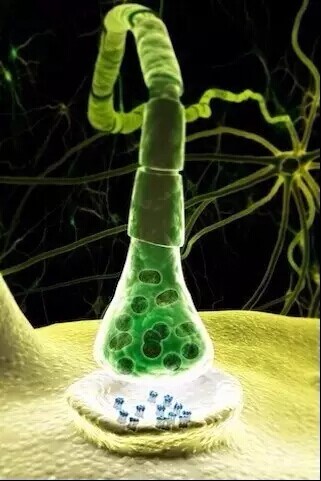

神经元

神经元

神经元